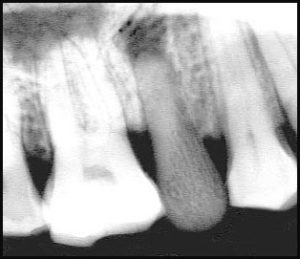

la texture du tissu osseux est la même chez ces mammifères, seule la morphologie change. Les radios que nous avons prises le confirment (fig.10).

L’examen radiographique montre une réelle contiguïté entre la paroi alvéolaire et la pseudo-racine. Nous en avons discuté avec le Professeur Marcel Gaspard de la Faculté de Chirurgie dentaire de

Paris ( Université R. Descartes ) et nous avons estimé qu’il était effectivement possible d’envisager que l’on ait là une cicatrisation par ostéogenèse sur 3 faces seulement, représentant , selon lui, un mode d’attache alvéolo-implantaire par ankylose ou par soudure de type » pleurodonte » dans lequel la dent est fixée uniquement par sa face vestibulaire à son support osseux (7).

Cette prothèse dentaire unitaire, endo-alvéolaire est un véritable implant en os. Il faut noter que la face occlusale dépasse très légèrement le sommet des autres dents. D’après ce qui a été écrit les antagonistes existaient et l’occlusion était impossible. mais si la mandibule n’est pas la sienne toutes les hypothèses sont envisageables y compris l’absence d’antagonistes.